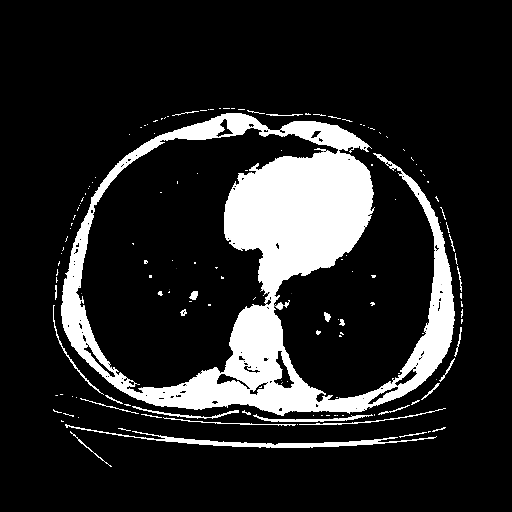

Original VENOUS CT scan

Full window (WL 1023.5, WW 4095 β†’ Low βˆ’1024, High +3071)

Actual HU range: [-1024.0, 3071.0]